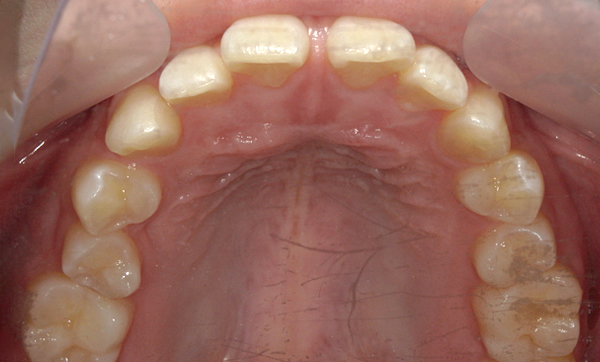

| 治療前 | 治療後 |

|---|---|

|